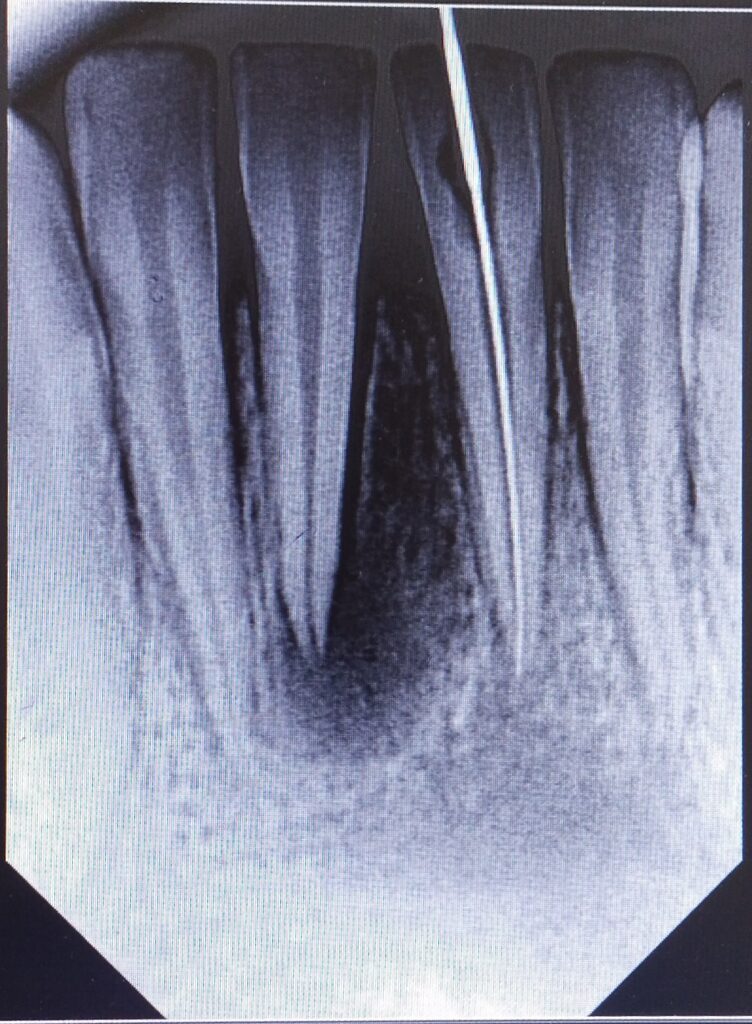

To assess the extent of the injury, we employed periapical X-rays, revealing radiolucency around the affected teeth. This indicated potential damage to the dental pulp and surrounding tissues, necessitating a strategic treatment plan.

Our approach focused on preserving Muzakkir’s natural dentition while promoting optimal healing. We opted for root canal treatment in the central incisors to address pulp involvement and prevent further complications. Additionally, we implemented a splinting technique, stabilizing the affected teeth from canine to canine to facilitate alignment and reduce mobility.